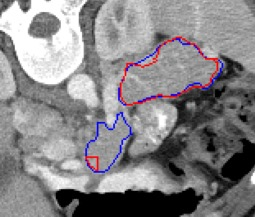

Automated segmentation in medical image analysis is a challenging task that requires a large amount of manually labeled data. However, most existing learning-based approaches usually suffer from limited manually annotated medical data, which poses a major practical problem for accurate and robust medical image segmentation. In addition, most existing semi-supervised approaches are usually not robust compared with the supervised counterparts, and also lack explicit modeling of geometric structure and semantic information, both of which limit the segmentation accuracy. In this work, we present SimCVD, a simple contrastive distillation framework that significantly advances state-of-the-art voxel-wise representation learning. We first describe an unsupervised training strategy, which takes two views of an input volume and predicts their signed distance maps of object boundaries in a contrastive objective, with only two independent dropout as mask. This simple approach works surprisingly well, performing on the same level as previous fully supervised methods with much less labeled data. We hypothesize that dropout can be viewed as a minimal form of data augmentation and makes the network robust to representation collapse. Then, we propose to perform structural distillation by distilling pair-wise similarities. We evaluate SimCVD on two popular datasets: the Left Atrial Segmentation Challenge (LA) and the NIH pancreas CT dataset. The results on the LA dataset demonstrate that, in two types of labeled ratios (i.e., 20% and 10%), SimCVD achieves an average Dice score of 90.85% and 89.03% respectively, a 0.91% and 2.22% improvement compared to previous best results. Our method can be trained in an end-to-end fashion, showing the promise of utilizing SimCVD as a general framework for downstream tasks, such as medical image synthesis and registration.